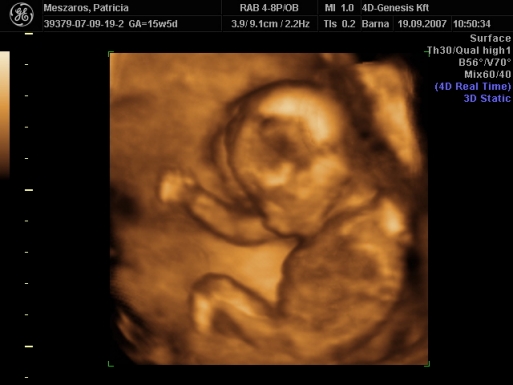

Üdv az újaknak! Itt valóban nagyon parás kismamák vannak, én az első 12 hetet végigparáztam, utána már csak mértékkel, de amióta mozog a bébi, meg láttam 4D-n, azóta oltári nyugodt vagyok...

Délután megyek a dokimhoz, terhesgondozásra, most kapok időpontot a következő UH-ra. Szerintem két hét múlva megyek, mert jövő héten sulihetem lesz, úgyhogy az kilőve. De most annyira nem is sürget a dolog, mivel a múlt héten volt a 4D.

Én is ajánlom mindenkinek a 4D-t, mi is nagyon jó helyet fogtunk ki, de mi vidéken, Szombathelyen voltunk, az van közel.

Egyébként mint megtudtam, ez a rendelő a Telki Magánkórház partnerintézete. Mondjuk elég luxus szinten mennek a dolgok, az biztos. De főleg az volt jó, hogy a szonográfus nő tök profi volt, és nagyon jól elmondott mindent, szinte minden részét láthattuk a kis kincsünknek, és még a nemét is megtudtuk kb. 9 perc után.

Szóval én nagyon meg voltam elégedve a szolgáltatással, egyébként 20 perces vizsgálat volt, szívhangot kihangosították, minden részét alaposan megnézték, kaptunk DVD-t, meg postán kapunk fényképeket. És ez volt 12.000 Ft.